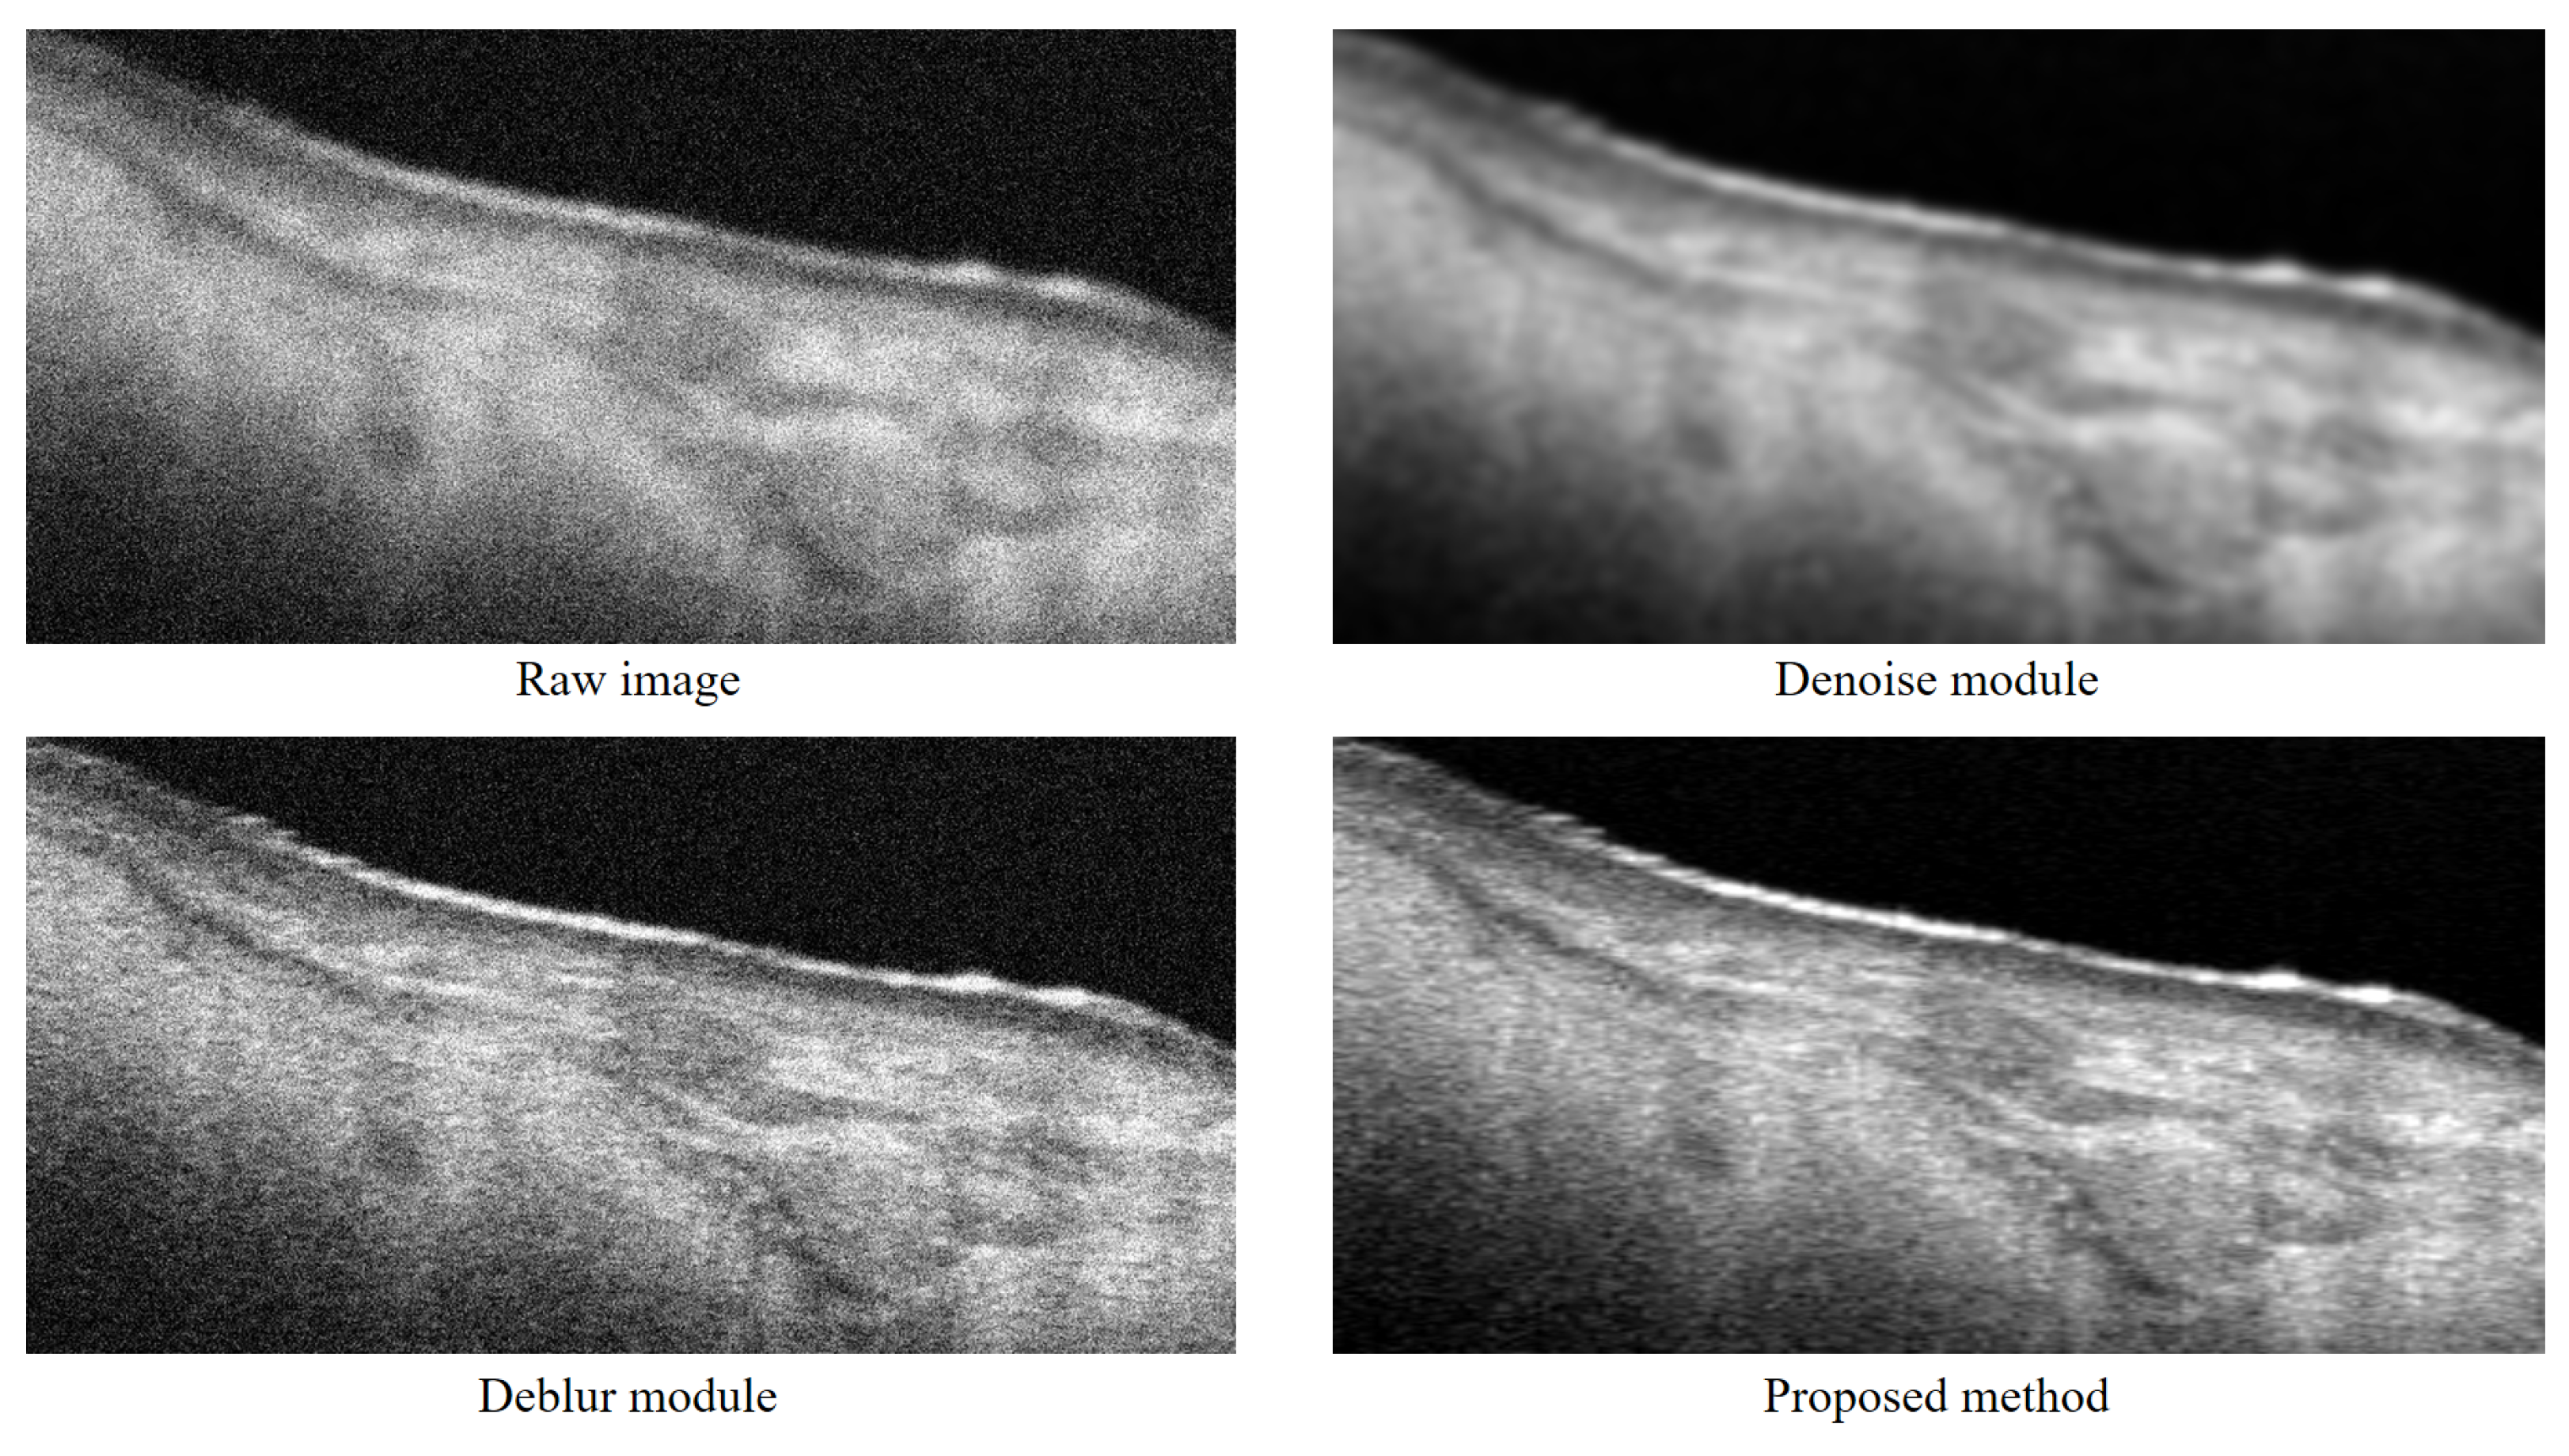

4.1. Ablation Study Results

| Metrics (Mean ± std) | ||

|---|---|---|

| Method | PSNR | SSIM |

| Original images | 8.94 ± 2.01 | 0.34 ± 0.14 |

| Denoise module | 19.53 ± 1.87 | 0.58 ± 0.20 |

| Deblur module | 17.55 ± 1.52 | 0.47 ± 0.12 |

| OSE | 26.71 ± 2.21 | 0.81 ± 0.16 |